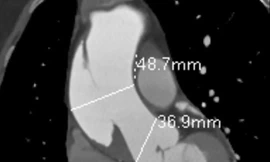

TPO - Nữ bệnh nhân nhập viện trong tình trạng bị đau ngực kéo dài không rõ nguyên nhân. Qua chẩn đoán hình ảnh, bác sĩ phát hiện bệnh nhân bị lóc thành động mạch, nguy cơ đột tử bất kỳ lúc nào.